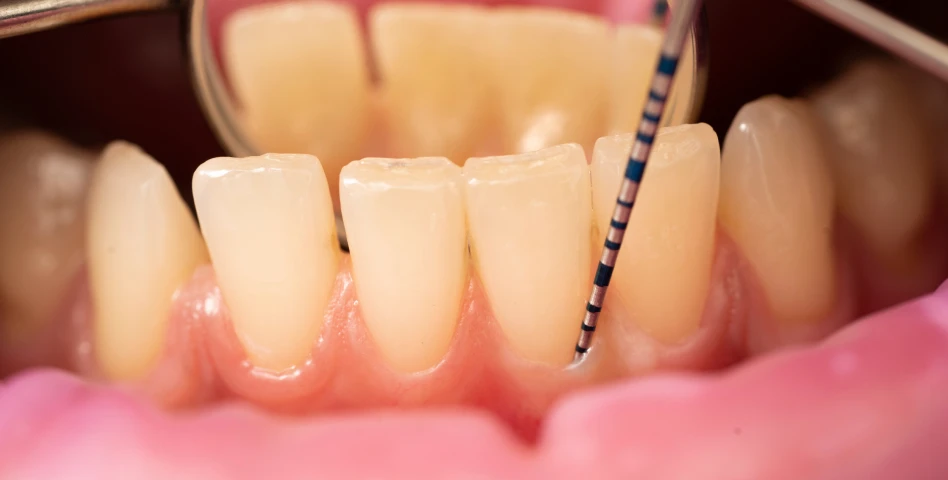

La plupart des patients, sauf contre-indications médicales sévères. Un bilan préalable (scanner, examens médicaux) est indispensable.